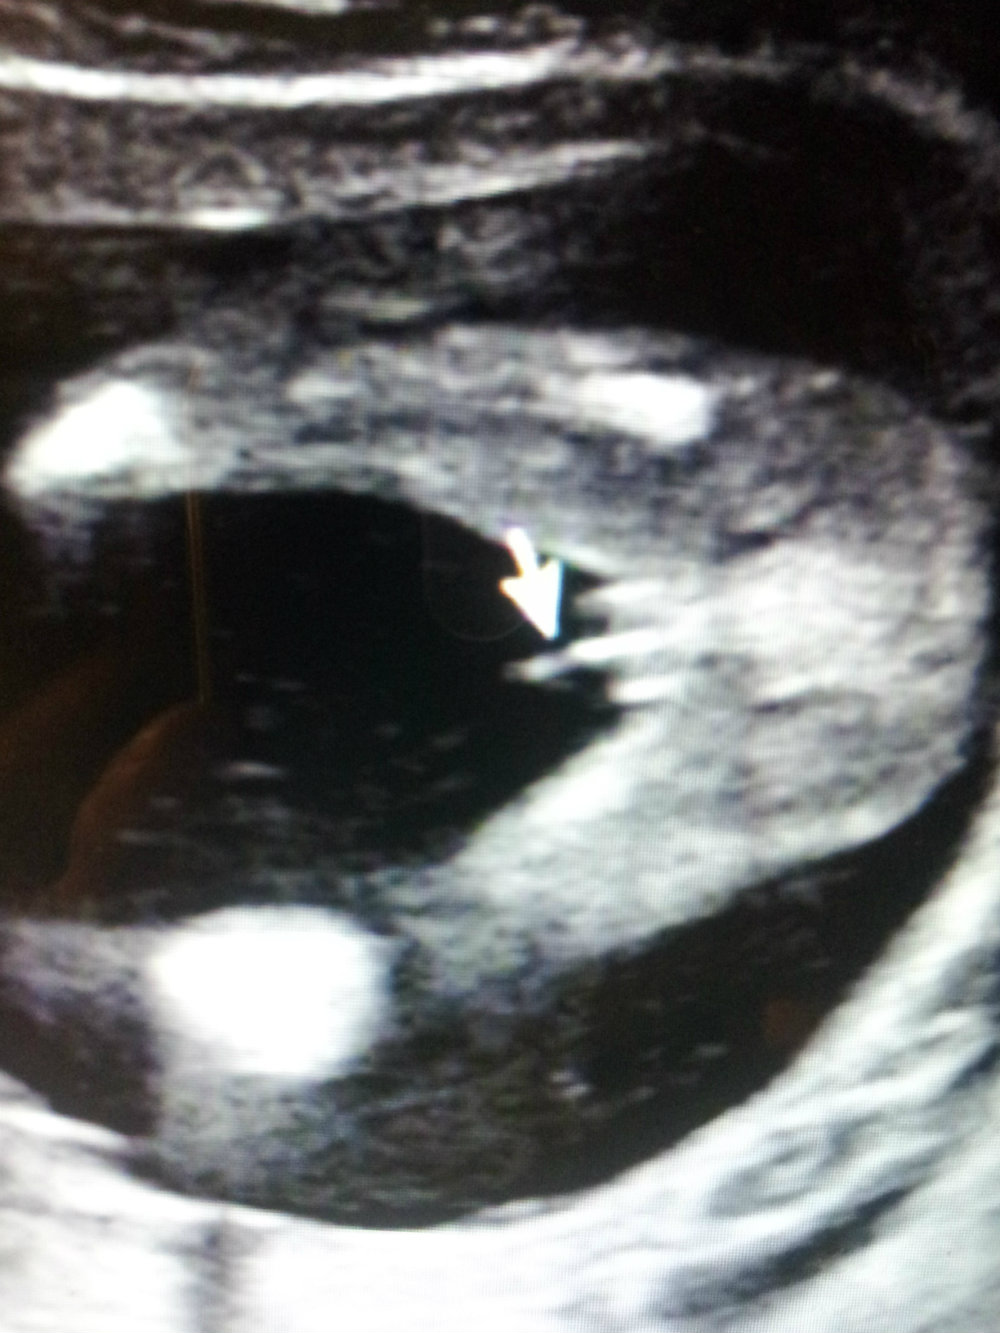

Recently had a 20 week ultrasound and was told 80% sure boy. We are thrilled with a boy but I always thought 3 lines means girl.. or is that just early on? Thanks!

Looks like a boy to me but not the best potty shot. There appears to be too much sticking out for that to be a girl. Boys can appear to have three lines too (my DS2's ultrasound is proof of this) because of the scrotum/penis being viewed at a certain angle.

What you have to understand is that boy and girl bits are really the SAME bits, it's just that hormones make them turn into boys and lack of hormones makes them turn into girls. So the bits do look somewhat similar when captured on the ultrasounds. Girls do have 3 lines but they don't have as much sticking out (esp at 20 weeks) Congrats on your boy!